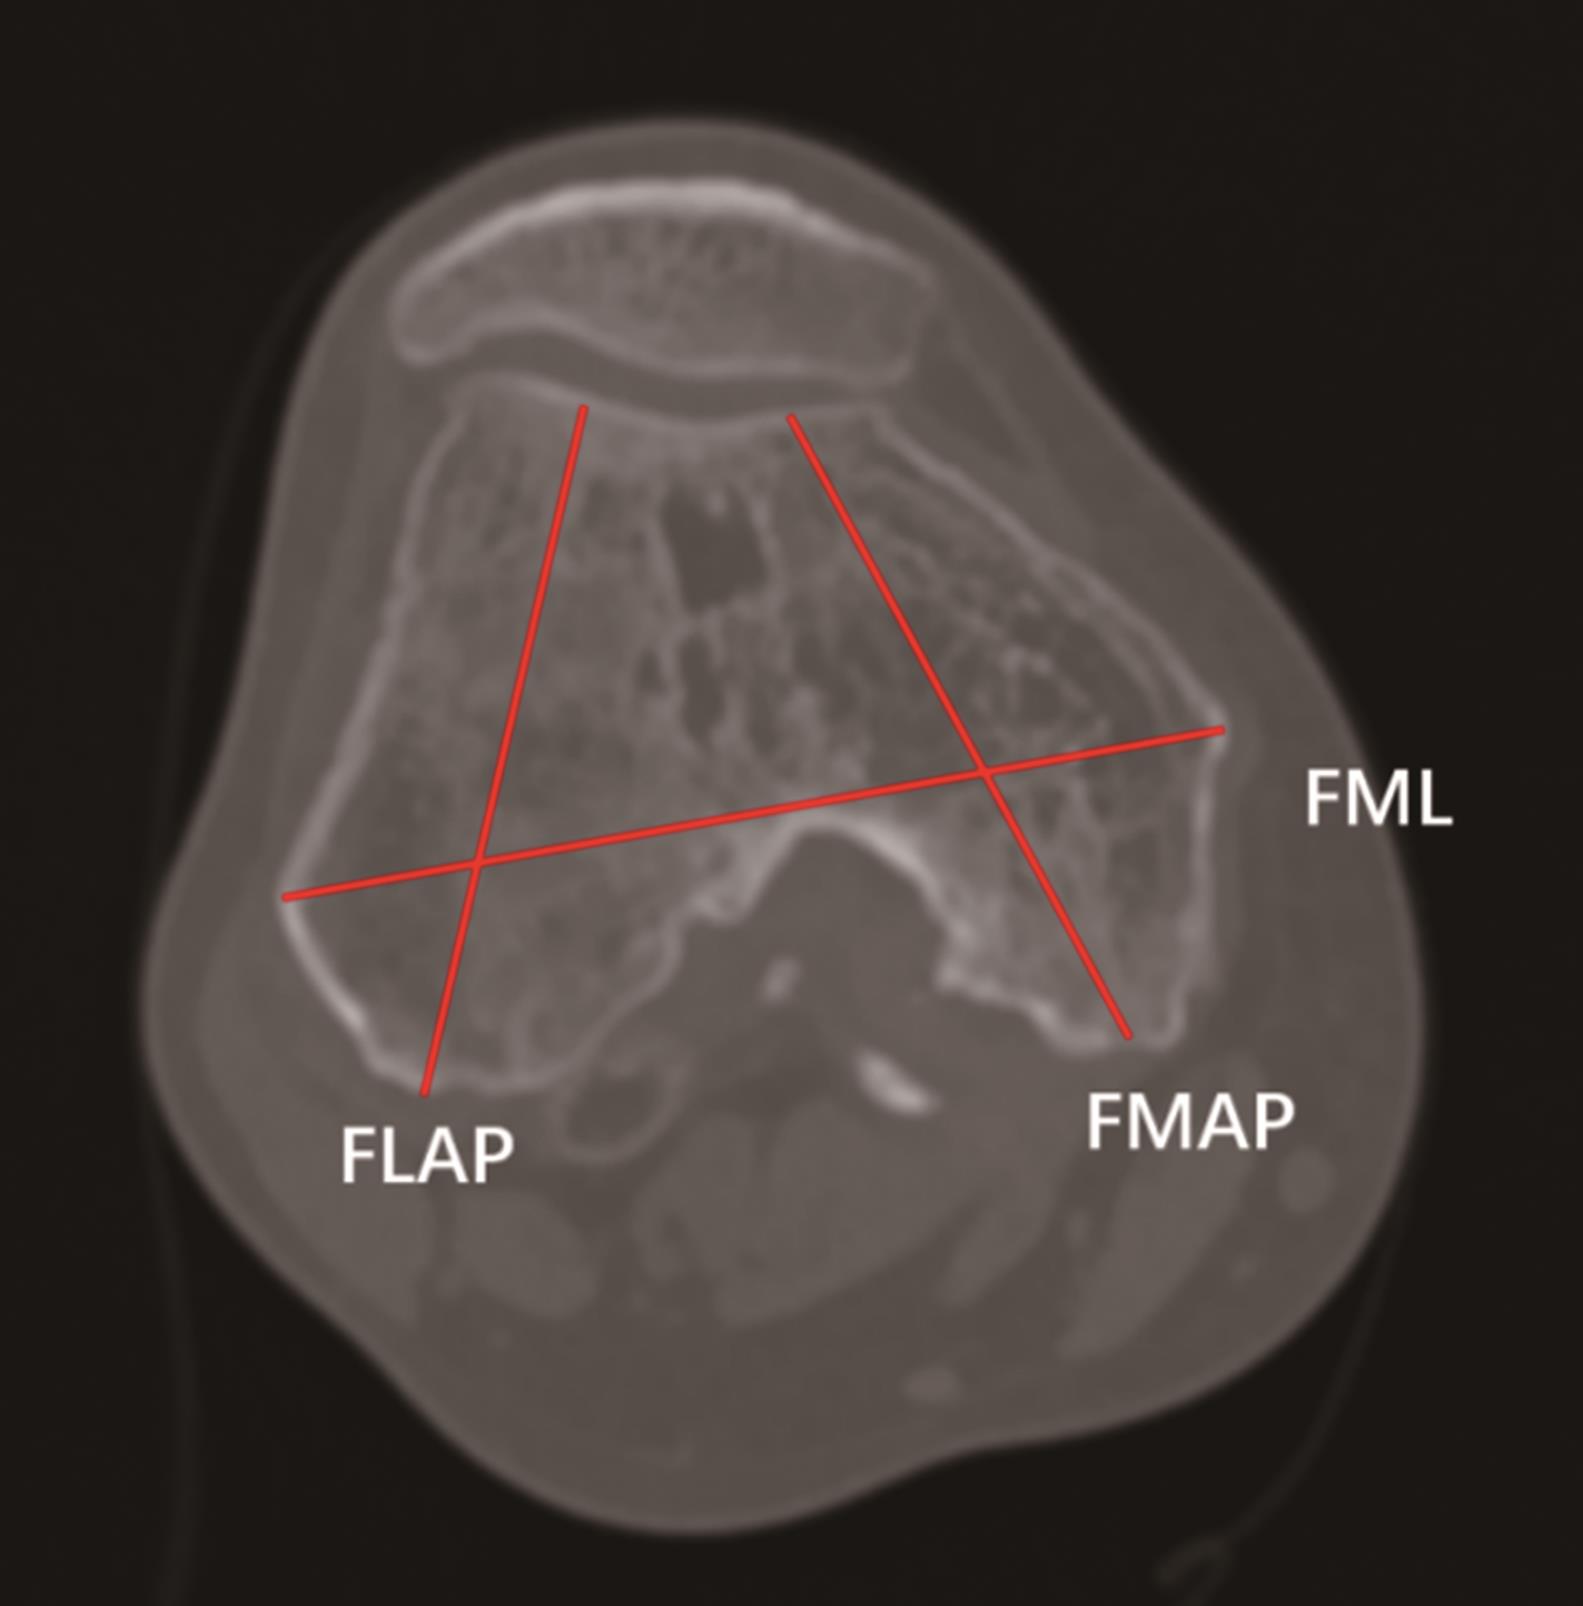

• 晚期大骨节病型膝关节炎患者CT参数分析

2024, 49(3):324-328. DOI: 10.13406/j.cnki.cyxb.

摘要 (67) HTML (69) PDF 1019.25 K (86) 评论 (0) 收藏

摘要:目的 分析晚期大骨节病型膝关节炎患者CT参数特点,为晚期大骨节病膝关节炎的诊断及膝关节置换术前设计提供参考。方法 回顾性分析重庆市人民医院创伤骨科2018年1月至2022年12月确诊的大骨节病膝关节炎患者,选择同期就诊的晚期膝关节骨性关节炎作为对照。用Mimics软件分析患者膝关节CT数据,测算膝关节骨赘体积、关节腔游离体数量、股骨髁内外侧横径(femoral mediolateral,FML)、股骨内侧髁前后径(femoral medial anteroposterior,FMAP)、股骨外侧髁前后径(femoral lateral anteroposterior,FLAP)、胫骨髁横径(tibial mediolateral,TML)、胫骨髁前后径(tibial anteroposterior,TAP)、胫骨内侧平台前后径(tibial medial anteroposterior,TMAP)、胫骨外侧平台前后径(tibial lateral anteroposterior,TLAP),并计算FML/FMAP、FML/FLAP、TML/TAP、TMAP/TLAP的比值。结果 共纳入70例患者,其中大骨节病组32例,骨关节炎组38例,2组患者在性别分布、平均年龄、体重指数上差异无统计学意义(P>0.05)。大骨节病组膝关节常形成多间室关节炎、关节周围有大量的骨赘形成、软骨下骨硬化。大骨节病组骨赘体积及关节腔内游离体数量更多(P<0.05),并且FML/FLAP、TMAP/TLAP大于对照组(P<0.05)。结论 晚期大骨节病膝关节炎患者退变征象更为明显,且股骨外侧髁、胫骨外侧平台前后径相对偏小,该影像学特点可为膝关节置换术前设计提供参考。